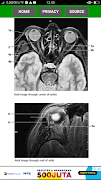

The key for any beginning radiologist who wishes to recognize pathological findings is to first acquire an ability to distinguish them from normal ones. This outstanding guide gives beginning radiologists the tools they need to systematically approach and recognize normal MR and CT images.

* Reference-quality images from the author's own teaching files show all standard normal findings as seen in CT and MRI